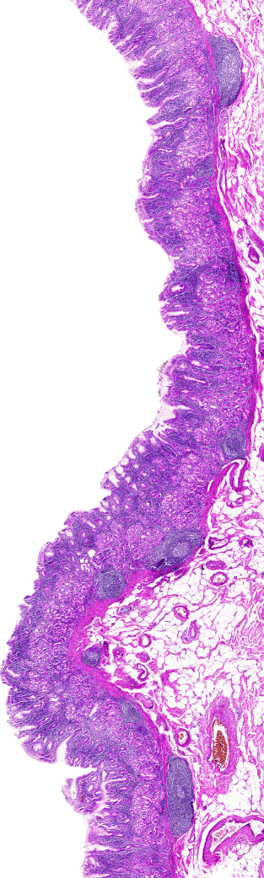

- Pathologists contribute to disease diagnosis through the examination of tissue samples, blood, and other bodily fluids. Trained specifically to read results for biological samples, pathologists work with a primary care physician (PCP) to identify and rule out diseases and conditions. Pathologists often sub-specialize in organ systems such as nerves/brain, kidney, blood and skin. Our certified dyes along with strict adherence to quality assurance procedures provide the foundation for products that provide pathologists with excellent morphological differentiation for their important role in identifying root causes for different symptoms.

- Laboratory Director is a board-certified medical doctor, PhD scientist or a medical laboratory scientist. Many are pathologists, using our stains and dyes to interpret biopsy results, pap tests and cytologic samples. An LD manages the overall operations with a laboratory.